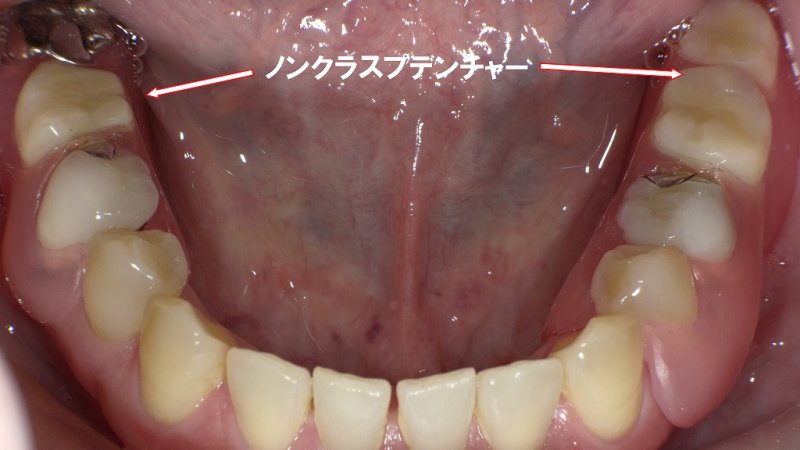

症例における適応

例えば、下顎大臼歯部に片側1歯、反対側2歯の欠損がある症例では、ノンクラスプデンチャーにより咬合支持を回復できます。

義歯床は歯肉に密着し、金属クラスプが見えないため審美的に優れます。必要に応じて金属レストを併用することで、沈下防止と咬合力分散を図り、機能性を高めます。